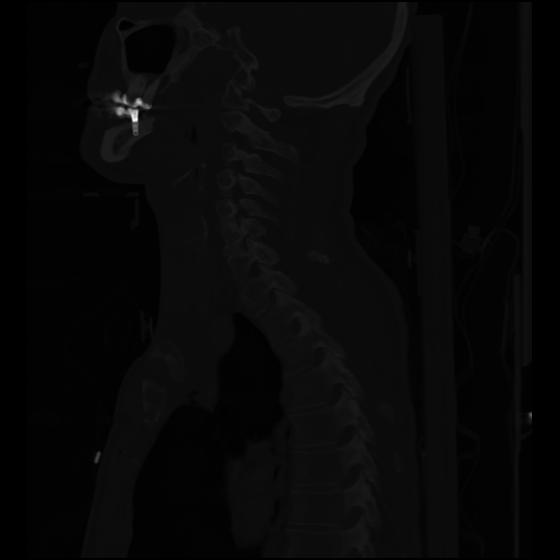

24 ANGIO,CE,Sag-MIP,5.000,ANGIO,Sag-MIP,